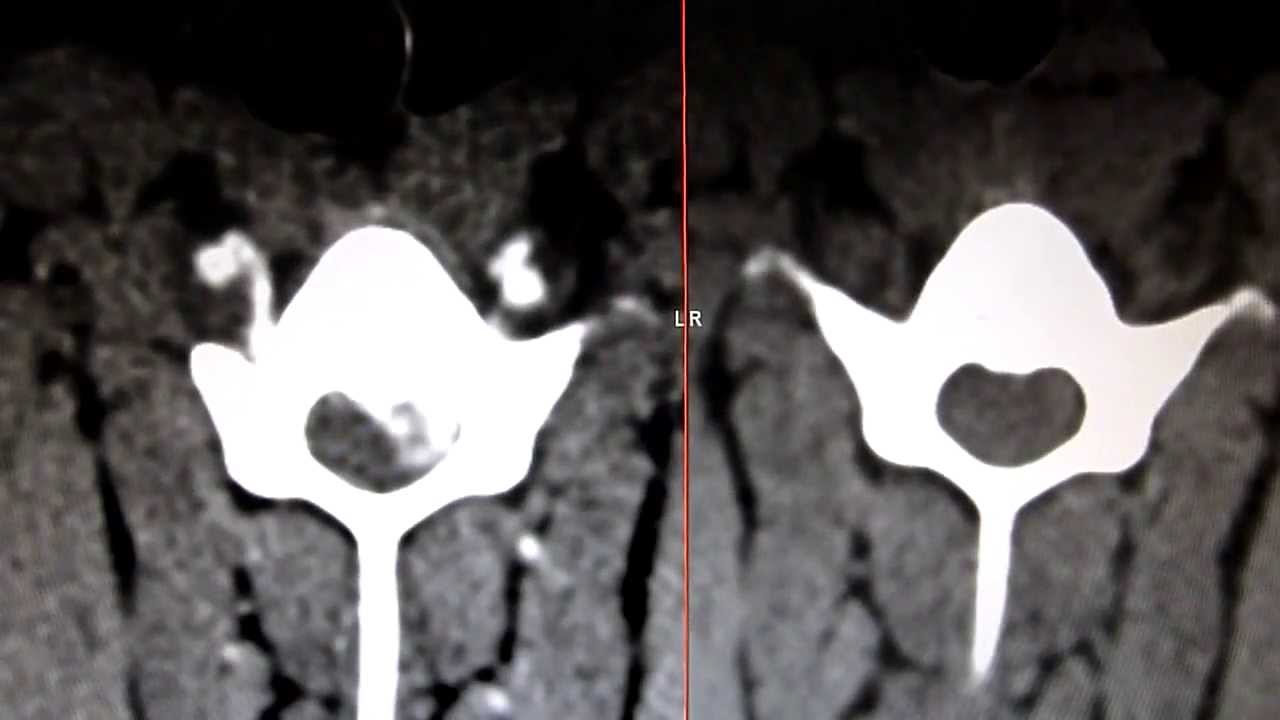

Tierklinik Schwanenstadt CT Bandscheibenvorfall beim Hund, pre und

CT_Wirbelsäule Bandscheibe Tierklinik Schwanenstadt